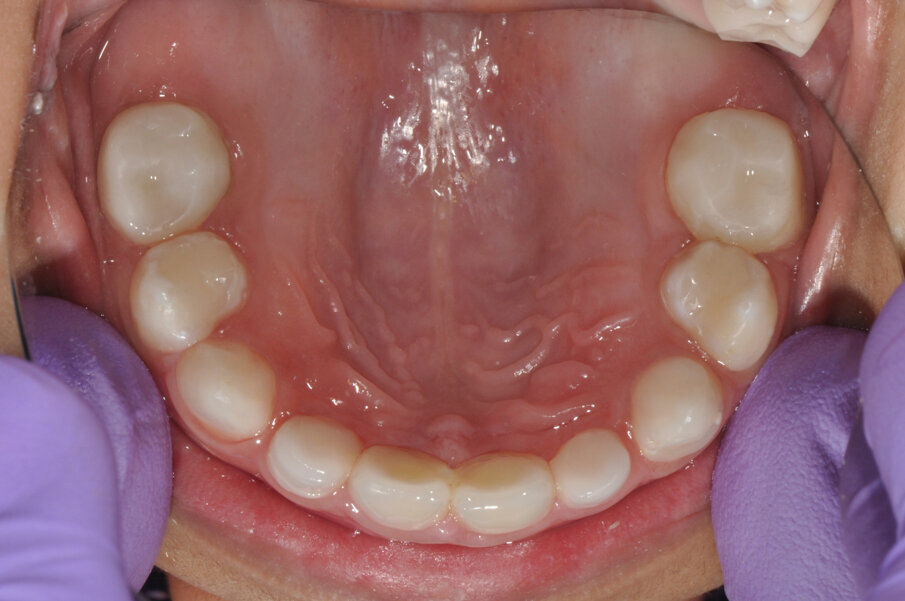

A 4-year-old girl was referred to the Children’s Dental Center in Gurgaon in India with the complaint of painful teeth when eating and the presence of unsightly maxillary anterior teeth. Clinical examination showed large carious lesions in the maxillary anterior teeth (Fig. 1). A radiographic examination showed pulpal involvement of caries in teeth #51 and 61 (Fig. 2).

Fig.1: Caries associated with the four front teeth.